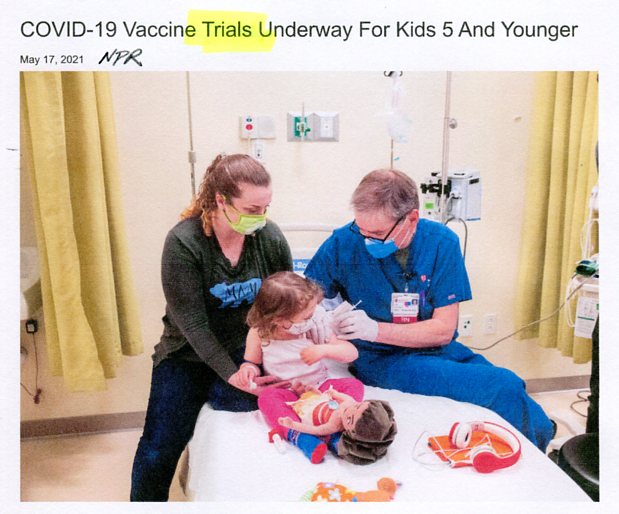

listen Parents allow Covid vaccine trials on their kids &

Covid vaccine experimental 6-month to 11-yr-old humans

watch Hideous truth of experimental COVID injections

(anyone getting jab after watching is beyond saving)